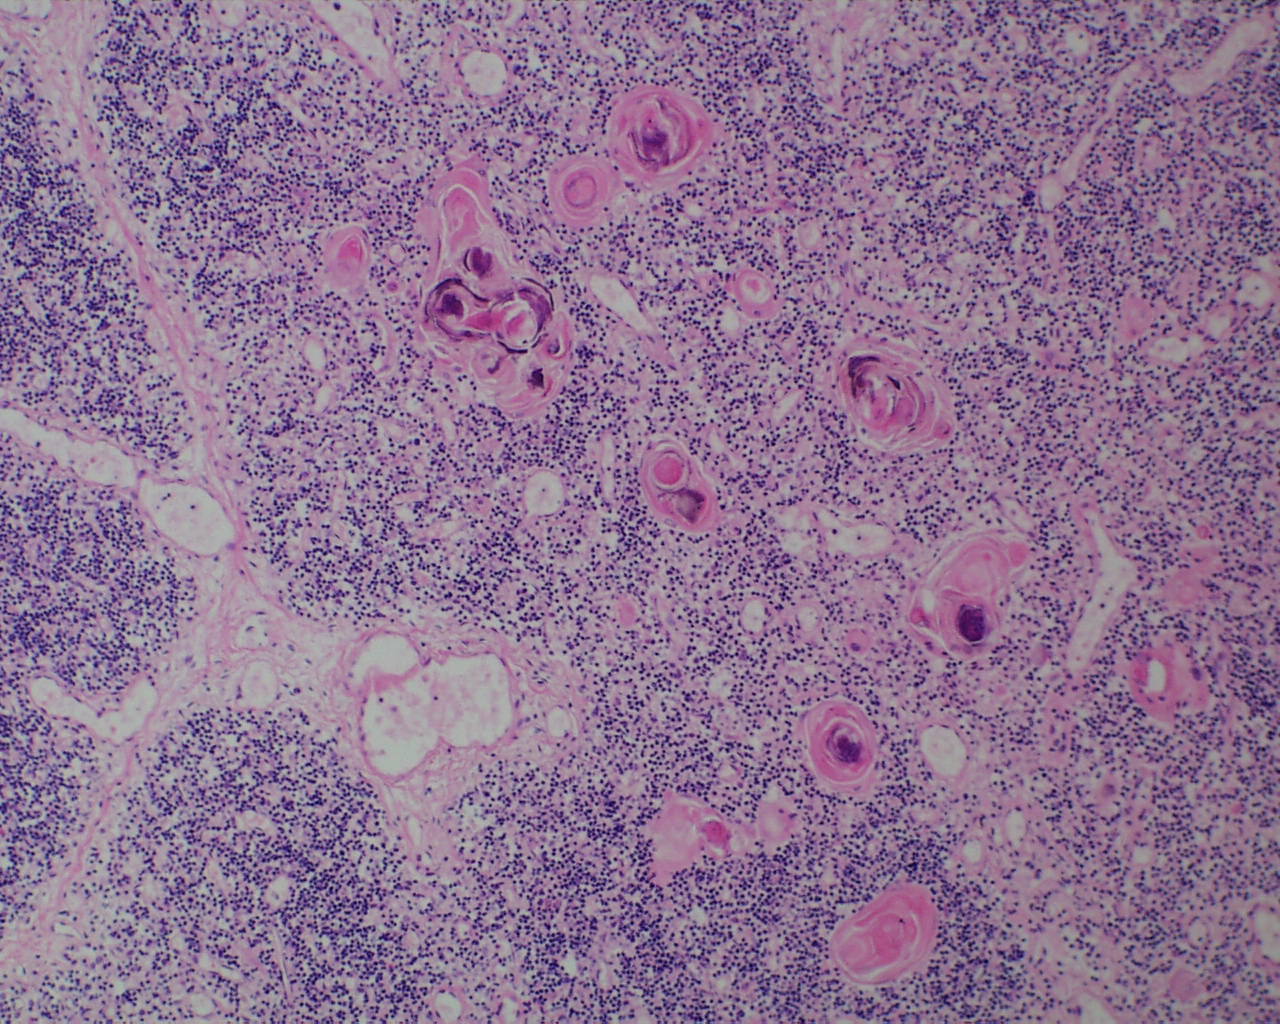

2. Thymic Involution

The thymus normally involutes as the infant ages. However, in some stillborn infants, usually with a chronic stress such as infection, fetal hydrops or growth restriction, there is accelerated involution, that is loss of the lymphocytes in the cortex of the thymus. An early phase of this process is often seen in response to chorioamnionitis. In the acute cases, the prominent abnormality is a “starry sky” appearance due to the lymphorrhagia (phagocytosis) of cortical lymphocytes. Low magnification microscopy demonstrates open spaces in the cortex reminding some observers of a “starry sky”. (Fig 9,10) At higher magnification, these apparent spaces can be seen to be the cytoplasm of a large cell often with small, fading nuclei of small lymphocytes within.

As involution progresses, there will be a progressive loss of cortical lymphocytes. The cortex will appear notably thinned compared to the medulla with thinner lobules and more connective tissue between lobules (Figs 11a, 11b, 12a, 12b, 13a, 13b).

At the extreme, the medulla will appear to have the only small lymphocytes in the thymus, giving an inside out appearance at low magnification (fig 14, 15).

A staging system has been proposed for this progression: stage 0 = no histopathologic changes, stage 2 = starry sky appearance, stage 3 = loss of distinction of the medulla and cortex, and stage 4 = loss of all cortical lymphocytes with an inverted appearance[16]. Based on the clinical histories, the stage has been correlated with duration of involution as follows: stage 0 = 0-12 hours, stage 1 = 12-24 hours, stage 2 24-48 hours, and stage 4 > 72 hours. A continuous stress keeps the thymus involuted, and results in decreased weight as demonstrated in human autopsy and in experimentally in the monkey with repetitive dexamethasone injections [17].The thymic to brain weight usually reflects the histological degree of involution when the small size is due to histological identified involution and not a failure of thymic development.